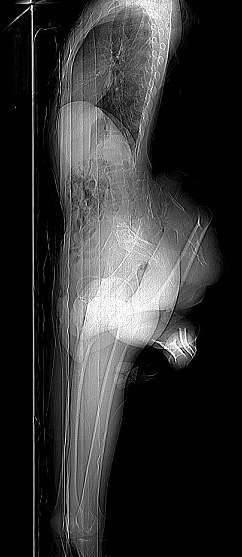

▼经过检查,他们发现Arun有多余的骨盆,详细情况还需要进一步检查。